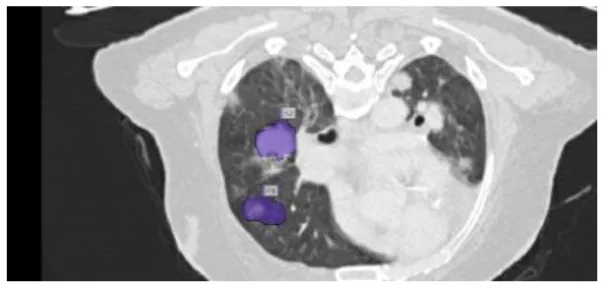

After preprocessing the image, shown in the Figure 11A the grouped picture, Figure 11B what was found when Lung tumors were identified. Figure 11C results of cutting lung tumors into whole pieces. Figure 11D the findings of the lung tumor search. Figure 11E picture showing the effects on a specific area of lung tumors when they are cut into pieces. Figure 11F a picture of a lung tumor that was accurately cut into pieces.

Figure 11

Utilizing the provided approach, we performed visual segmentation of heterogeneous lung nodules. (A) Clustered image. (B) Segmented image. (C) Extracted image. (D) Extracted image with nodules localizations. (E) Nodule capture. (F) Nodule region highlighted.